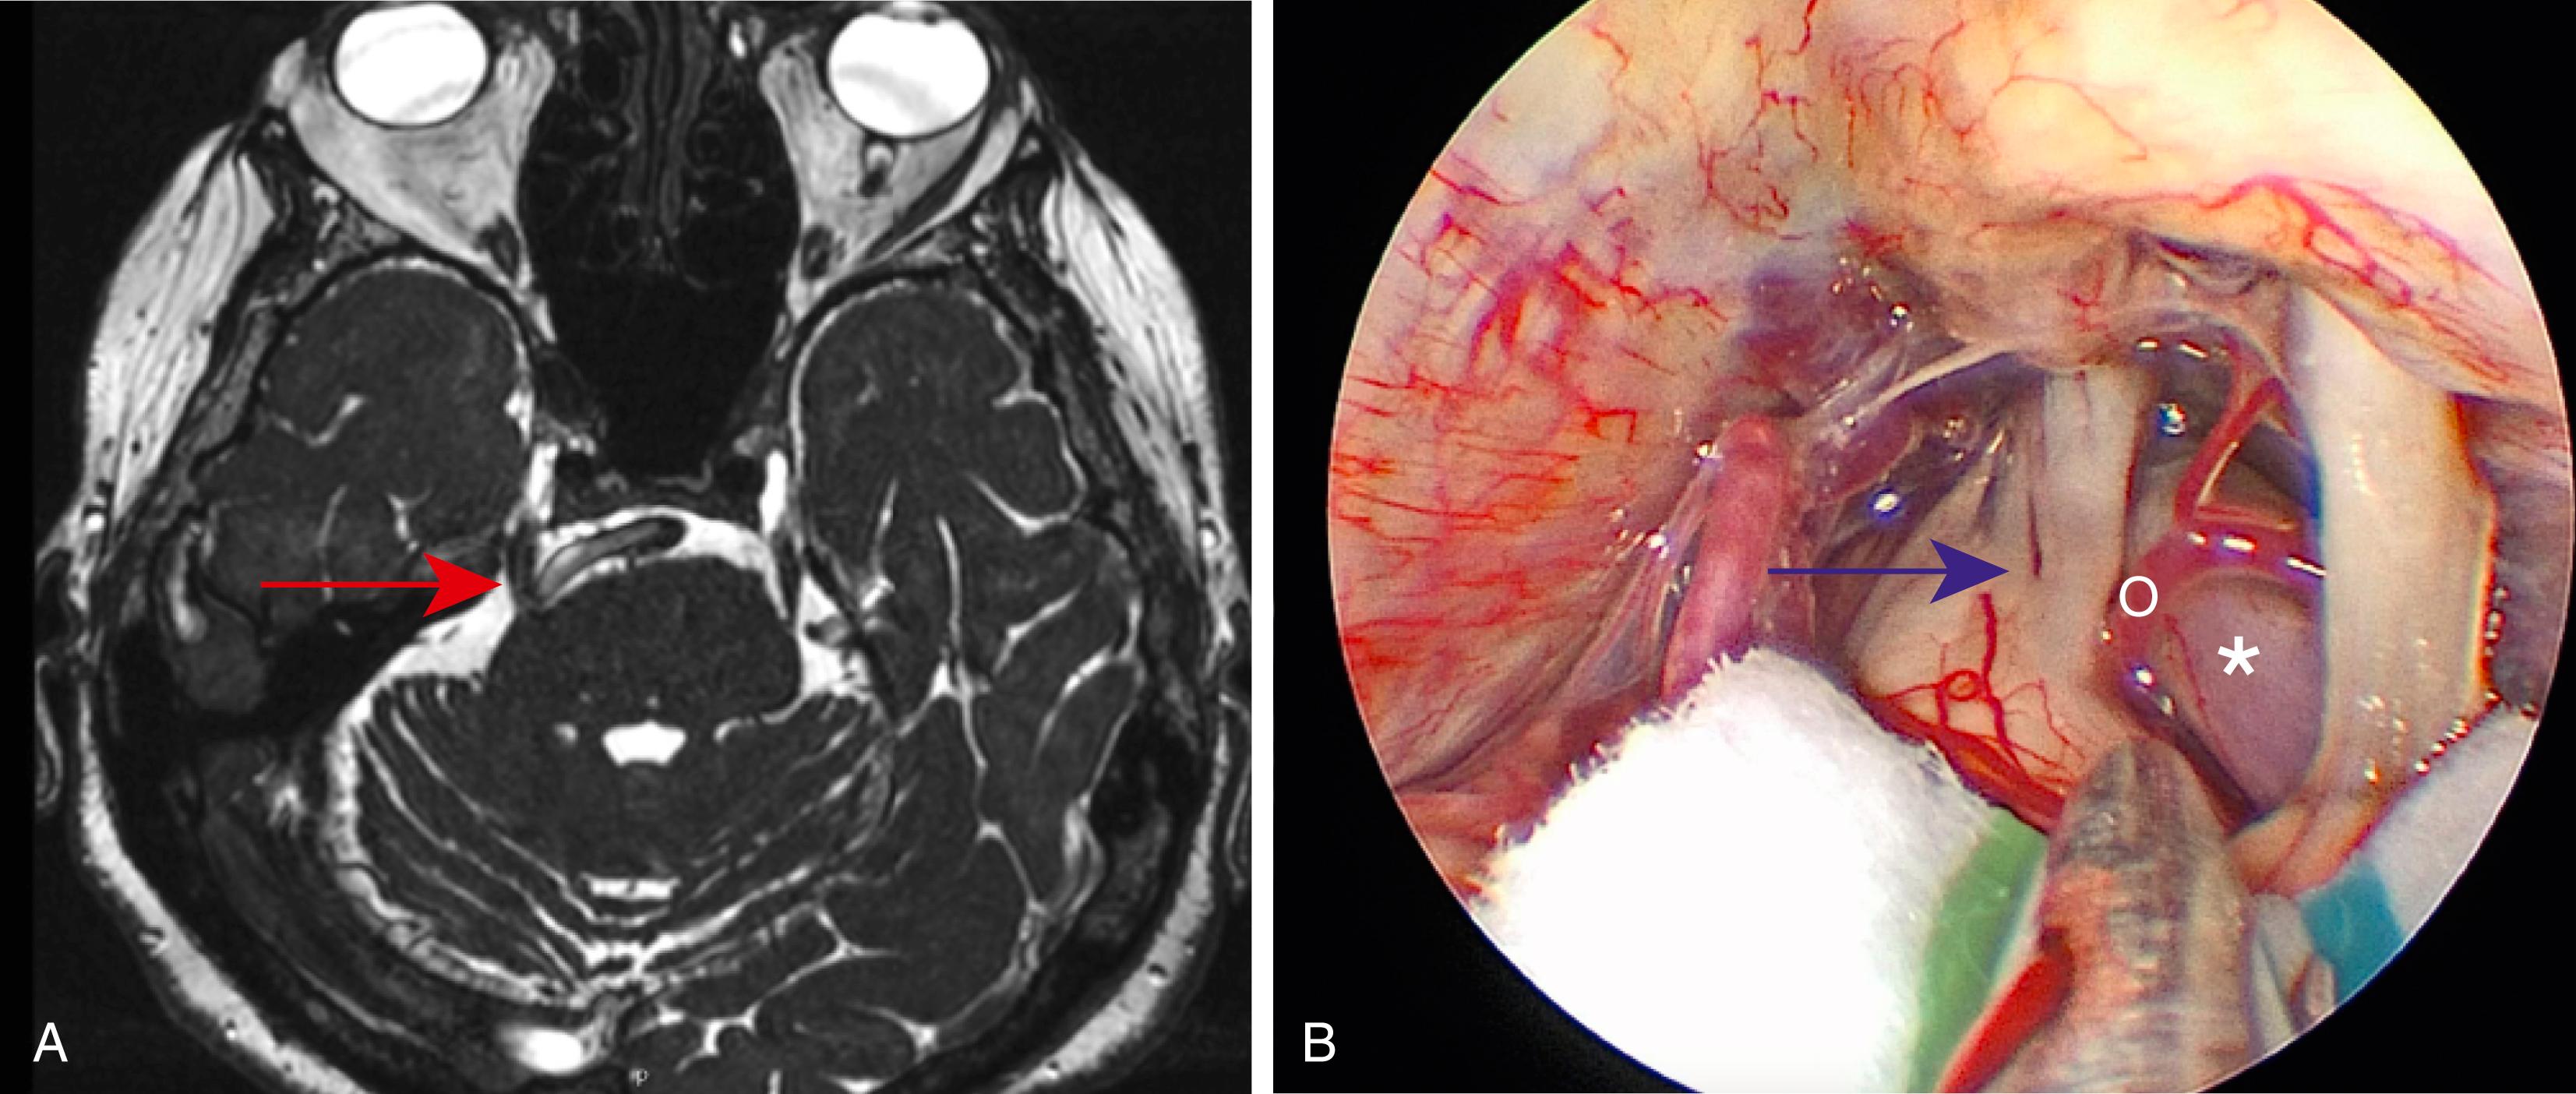

Here, we will describe each of the vascular compressive syndromes, including TN, hemifacial spasm, and GN. Prior to specific discussion, it is important to consider that these syndromes remain clinical diagnoses. Each syndrome has a stereotyped clinical presentation existing within a spectrum of severity. A thorough history including the character and location of pain, frequency of episodes, and triggers is imperative for an accurate diagnosis. Because of the significance of the clinical history, radiographic imaging is not necessary for the clinical diagnosis of vascular compressive syndromes. However, it remains an important part of the workup, as it can demonstrate nonvascular compression (e.g., mass lesion), which can drastically alter an operative plan should a patient be considered for surgery. MRI is the preferred imaging modality. We favor FIESTA (Fast Imaging Employing STeady-state Acquisition) MRI for optimal delineation of cranial nerves within cerebrospinal (CSF) spaces ( Fig. 39.1 ). Other institutions use vascular imaging with 3D reconstructions.

Fig. 39.1, Comparison of FIESTA (Fast Imaging Employing STeady-state Acquisition) MRI and intraoperative findings.